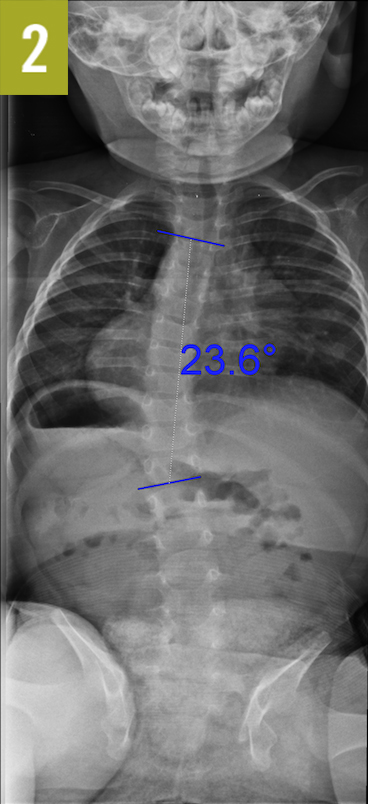

Diagnostic tests. With 2 of 3 criteria needed for VACTERL association (Table), renal ultrasonography was ordered, the results of which were normal. The initial radiograph of the spine showed a left-sided thoracic curve with a Cobb angle of 20°. Repeated imaging 4 months later showed progression of the curve to 24° and a rib vertebra angle difference (RVAD) of less than 20° (Figure 2). Therefore, the patient received a diagnosis of infantile idiopathic scoliosis (IIS).

Discussion. Idiopathic scoliosis affects up to 3% of children, with 1% of those cases being IIS diagnosed before age 3 years.1,2 Because IIS is often associated with plagiocephaly and hip dysplasia, it is thought to be a positional deformity. While AIS (adolescent idiopathic scoliosis) is more common in girls than in boys, IIS has a male to female ratio of 3 to 2.1 IIS is a diagnosis of exclusion and is made when other causes, such as neuromuscular disorders, vertebral malformations, and syndromic disorders such as VACTERL association, have been ruled out. Curves can be progressive or nonprogressive, and a Cobb angle of 20° or more or an RVAD of 20° or more predicts progression.3 If the RVAD exceeds 20°, magnetic resonance imaging scans show that approximately 20% of patients have neuroanatomical abnormalities such as Chiari malformation.4